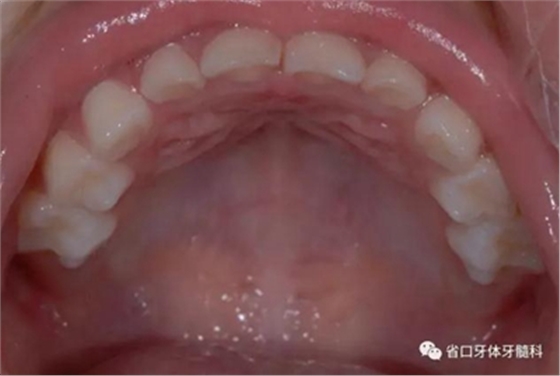

圖7 上頜牙相

圖14/15 矯治結(jié)束后45度牙相

圖16 矯治結(jié)束后上頜牙相